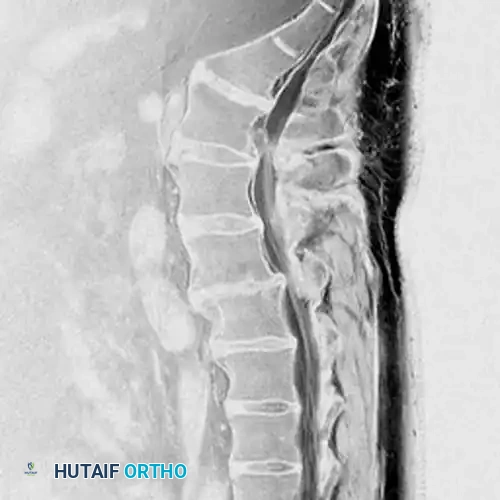

Diagnostic Imaging

Advanced neuroimaging is critical for preoperative planning. Magnetic Resonance Imaging (MRI) remains the gold standard, providing unparalleled visualization of neural elements, disc hydration, and the exact morphology of the herniation.

Sagittal sequences are essential for evaluating the craniocaudal extent of extruded disc fragments, assessing Modic changes in the endplates, and ruling out tandem lesions or conus medullaris pathology.